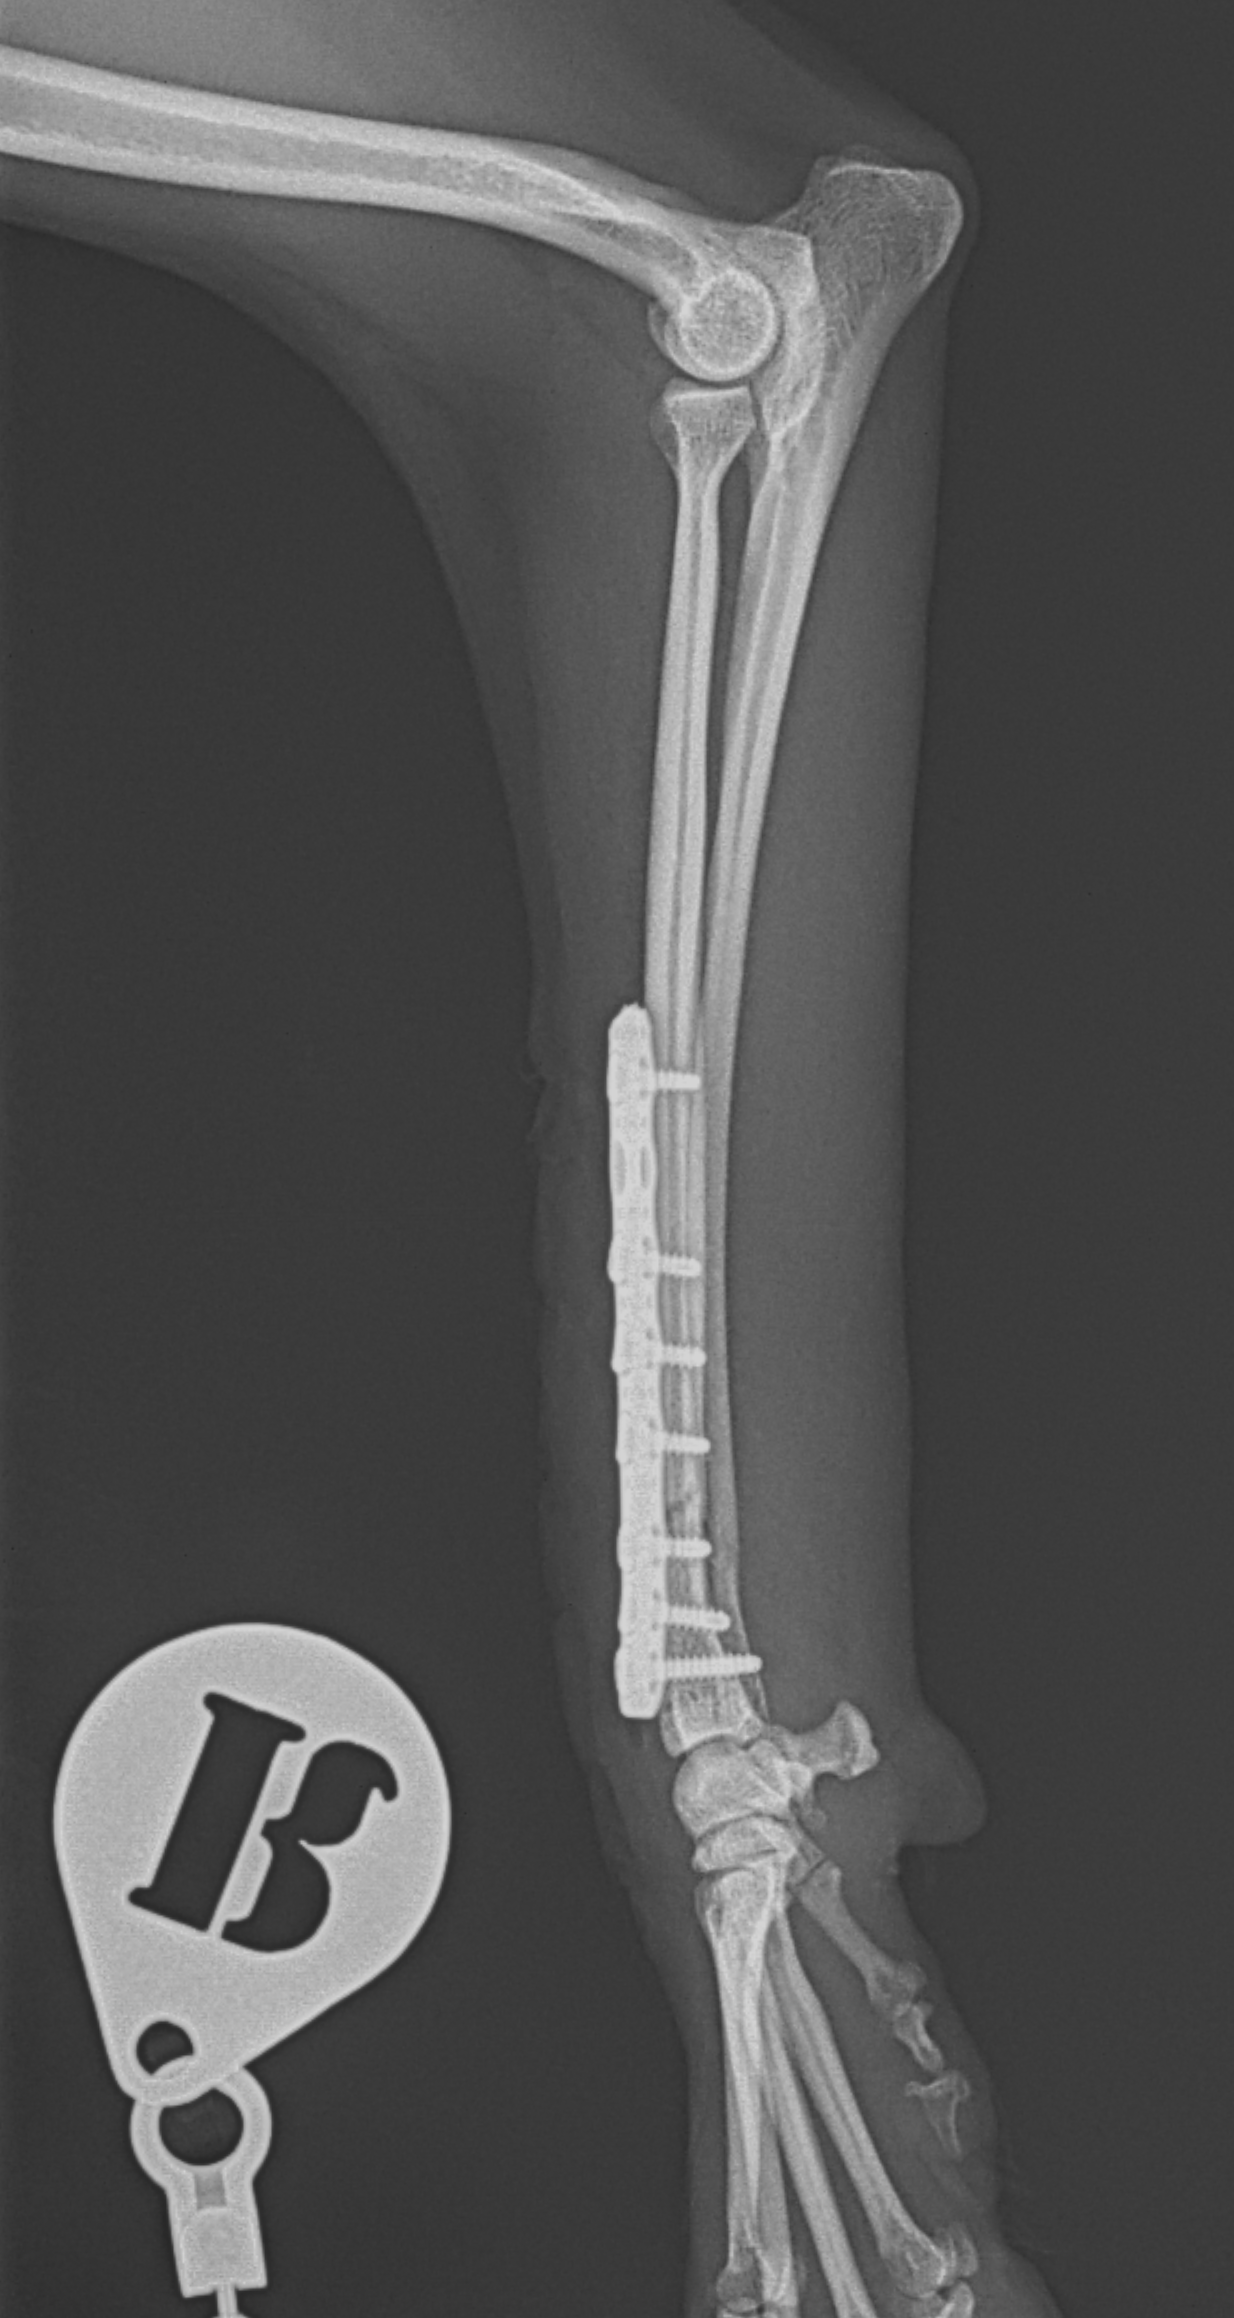

Tea Cup Poodleさんが、ご家族が家に帰宅すると足を挙上しており、着地できないとの事。室内で転倒したか、ソファーなどからジャンプして着地に失敗した可能性があります。エックス線検査で橈骨遠位端骨折が確定されました。1.5mm 3hole タイト ピッチ ストレートプレートで遠位端を固定しました。しばらくは安静が必要です。